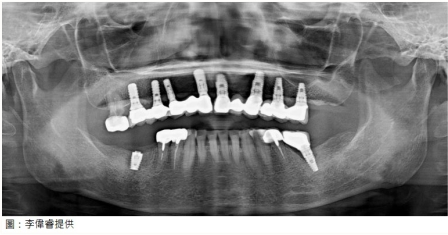

口腔癌易「多發」,仔細追蹤很重要